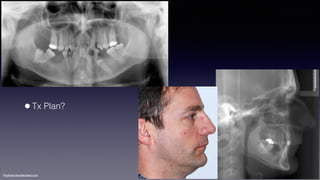

•Tx Plan?

•Retrognatic maxilla and mandible

•Mx incisors retroclination

•Md incisors proclination

Tx plan

•Apectomy #42

•Perio evaluation and clearance

•Alleviate dental compensation

•Arch coordination

•Orthognatic surgery: maxillo-mandibular advancement